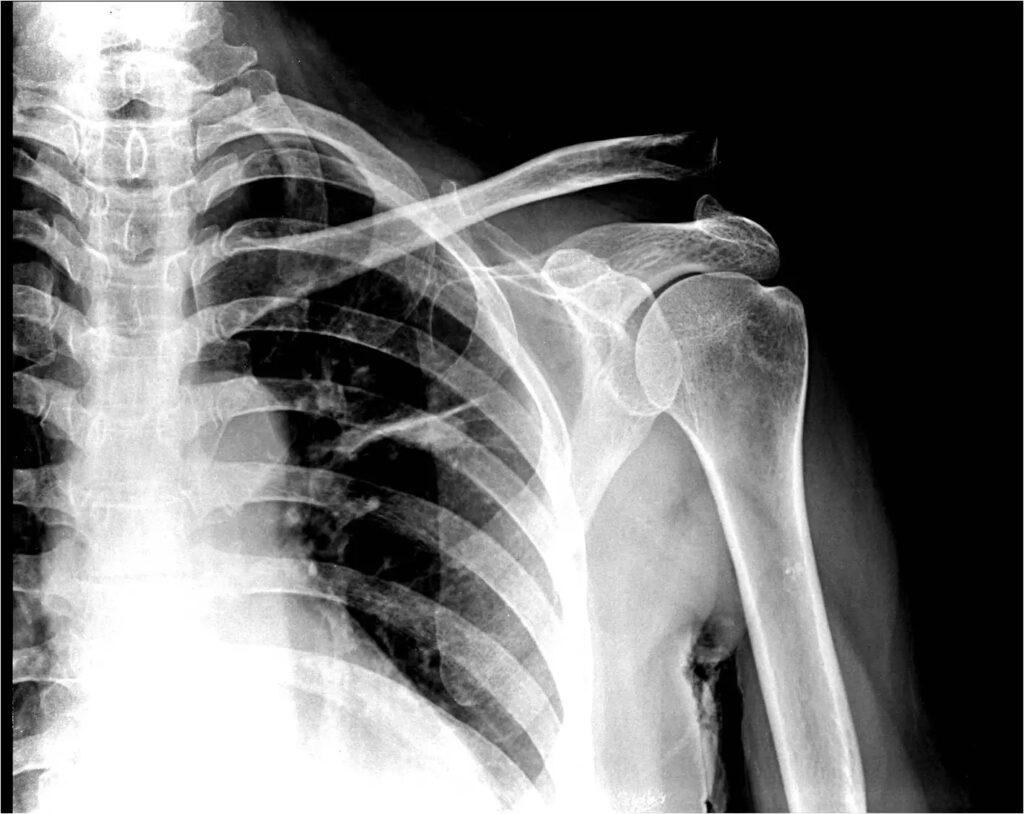

Una vez en el hospital, necesitarás radiografías para confirmar si te has roto la clavícula. Una fractura de clavícula generalmente se trata en el hospital.